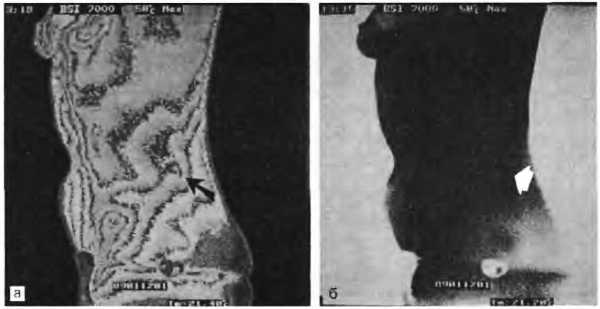

Рис. 4.10. На термограмме больного с триггерной точкой в левой квадратной мышце поясницы виден «горячий узел» (указан стрелками) не менее 0,5 °C над областью мышцы. Термограмма была выполнена при помощи системы Bales Scientific МСТ 7000:

22